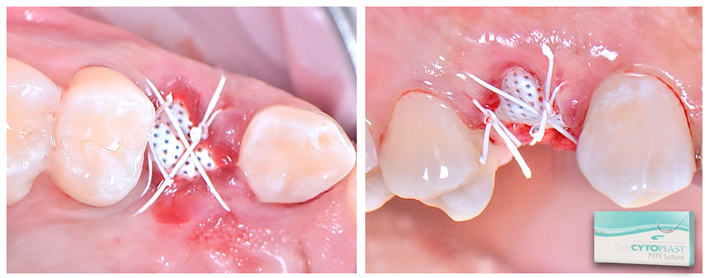

Após o diagnóstico e planejamento, baseados em exames radiográficos e clínicos (Figuras 1 e 2), a primeira etapa foi realizar uma extração dentária atraumática (secção dentária e utilização de periótomo fino e flexível), visando a preservação completa do periodonto de sustentação. Após a curetagem para remoção total da lesão periapical, fez-se a instalação do implante alcançando-se um ótimo travamento inicial e um correto posicionamento ápico/coronal e tridimensional (Figura 3). O Túnel Check, da Implacil De Bortoli (Figura 4), foi utilizado para avaliar o posicionamento tridimensional do implante e selecionar a altura correta do cicatrizador – optou-se por um cicatrizador ao invés do parafuso de cobertura do implante para que não houvesse formação óssea sobre o parafuso, o que tornaria a reabertura muito mais traumática. Após, a membrana Cytoplast TXT 200 Singles (Implacil De Bortoli) foi personalizada e instalada inicialmente na face palatina (Figura 5 – ela não deve ficar tocando nas faces proximais dos dentes vizinhos), seguido do preenchimento alveolar (Figura 6) com substituto ósseo natural contendo 25% de colágeno, o Extra Graft XG-13 (Implacil De Bortoli). Por conter colágeno na sua composição, o Extra Graft XG-13 não fica liberando as partículas ósseas ao longo do processo de osteointegração.

Finalizada a compactação do enxerto ósseo no sítio alveolar (Figura 7), o alvéolo foi selado com a membrana (Figura 7) e realizou-se a sutura com o fio Cytoplast, da Implacil De Bortoli (Figura 9), que é monofilamentar e feito em PTFE (Politetrafluoretileno). Essas características resultam em menor agregação bacteriana e em certa elasticidade do fio, o que reduz a chance de deiscência da sutura, uma vez que ele acompanha o deslocamento do tecido durante a inflamação e aumento de volume. Quatro semanas após a cirurgia, a sutura e a membrana foram removidas (Figuras 10 e 11). Como a membrana não é absorvível, ela deve ser removida entre 21 e 28 dias após a sua instalação. Após o período de 90 dias, realizou-se uma nova tomografia para se avaliar o correto posicionamento tridimensional do implante e a osteointegração (Figura 14).